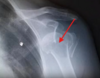

# Voici une vue axillaire, votre dx?

normale (pas de luxation) ## Footnote si déplacé vers acromion = post vers coracoide = ant